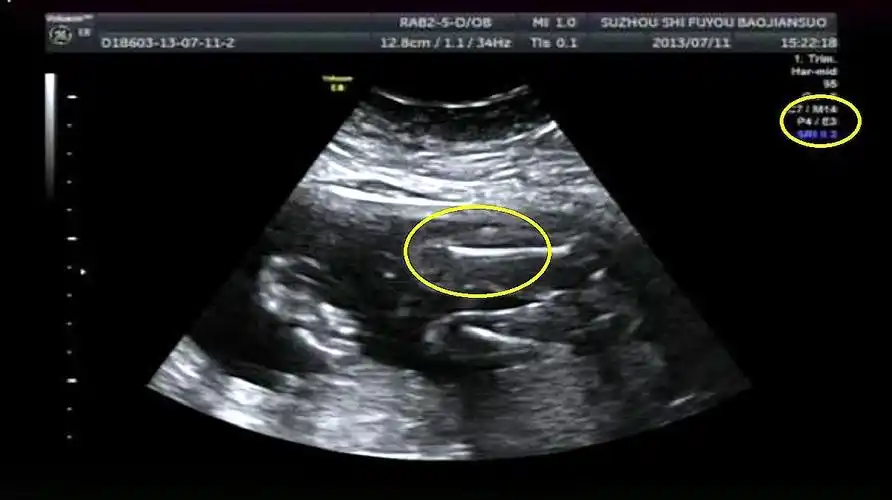

辨别胎儿性别有方法,b超单上一清二楚,再也不用求医生了!

眼看着孕期已经3个月,但b超检查却怎么也找不到子宫里的胎儿